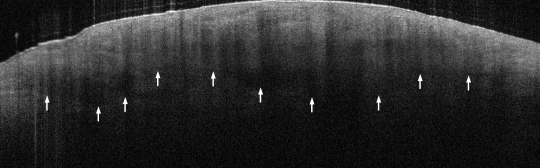

VA15: Right Dorsal Hand, Squamous Cell Carcinoma, Invasive, Keratoacanthoma type

- Arrows indicate extent of squamous mass